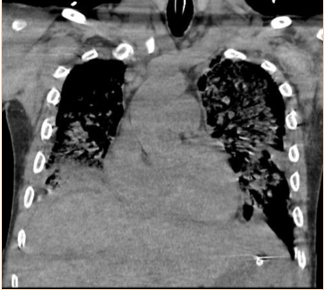

Abstract: We report a case of a 34 year old male with AIDS who presented to the hospital with abdominal pain and dyspnea. He received a comprehensive work-up including extensive imaging and biopsies revealing high grade mature B-cell lymphoma with features consistent with Burkitt’s Lymphoma with concomitant Ebstein Barr viremia. This case demonstrates the need for vigilance when assessing patients with HIV or AIDS for lymphoma with vague complaints and no identifiable source of infection.References